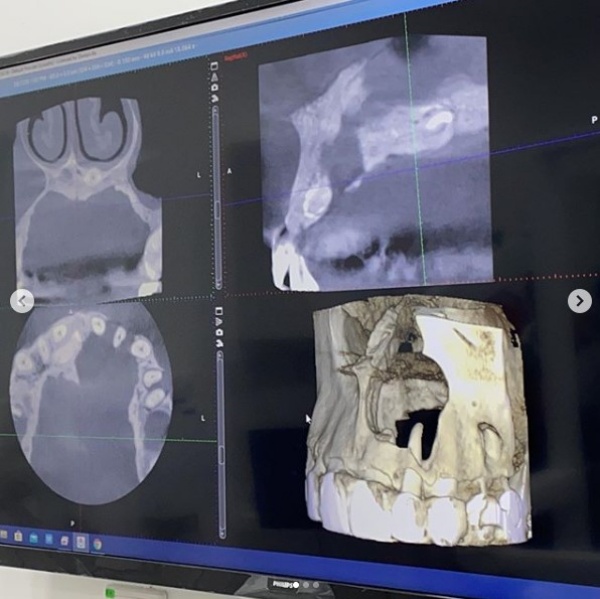

Danny解释,2年前开始牙龈发炎,但自己没有多加理会,结果导致发炎恶化、肿大甚至还会出脓。经医生诊断,Danny的牙龈和骨头开始被细菌侵蚀。在他贴出的X光照片中看到,Danny的鼻孔下已经出现一个无底洞,“医生说,说不定以后会毁容,真的很严重,差不多要到鼻子去了!再不开刀可能鼻子就会穿洞了…”。

过后就去检查发现牙龈和骨头被细菌侵蚀了(看图二)

鼻孔下一个很大的无底洞(医生说,说不定以后会毁容)

真的很严重,差不多要到鼻子去了!

再不开刀可能鼻子就会穿洞了…